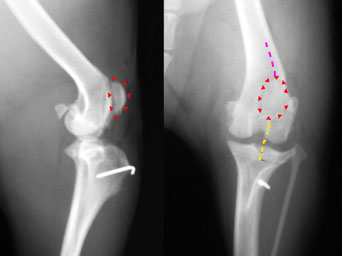

写真上段: 手術前

大腿直筋(紫点線)から膝蓋骨(赤△で囲んだところ)を経て膝蓋靱帯(黄色点線)とつながるラインが大腿骨の中心から内側にずれてしまっています。このため、膝蓋骨は大腿骨滑車(緑2本線)から外れて(脱臼)います。また足首を前方向きにして撮影しているにもかかわらず、膝蓋靱帯が脛骨(下腿骨)に付着する脛骨粗面が内側に変位しています。

大腿直筋−膝蓋骨−膝蓋靱帯のラインが大腿骨の中心を通り、膝蓋骨が大腿骨滑車の中におさまるようになっています。脛骨粗面は正面寄りに移動されています(白く写る線は、移動した骨片を留めているピン)。